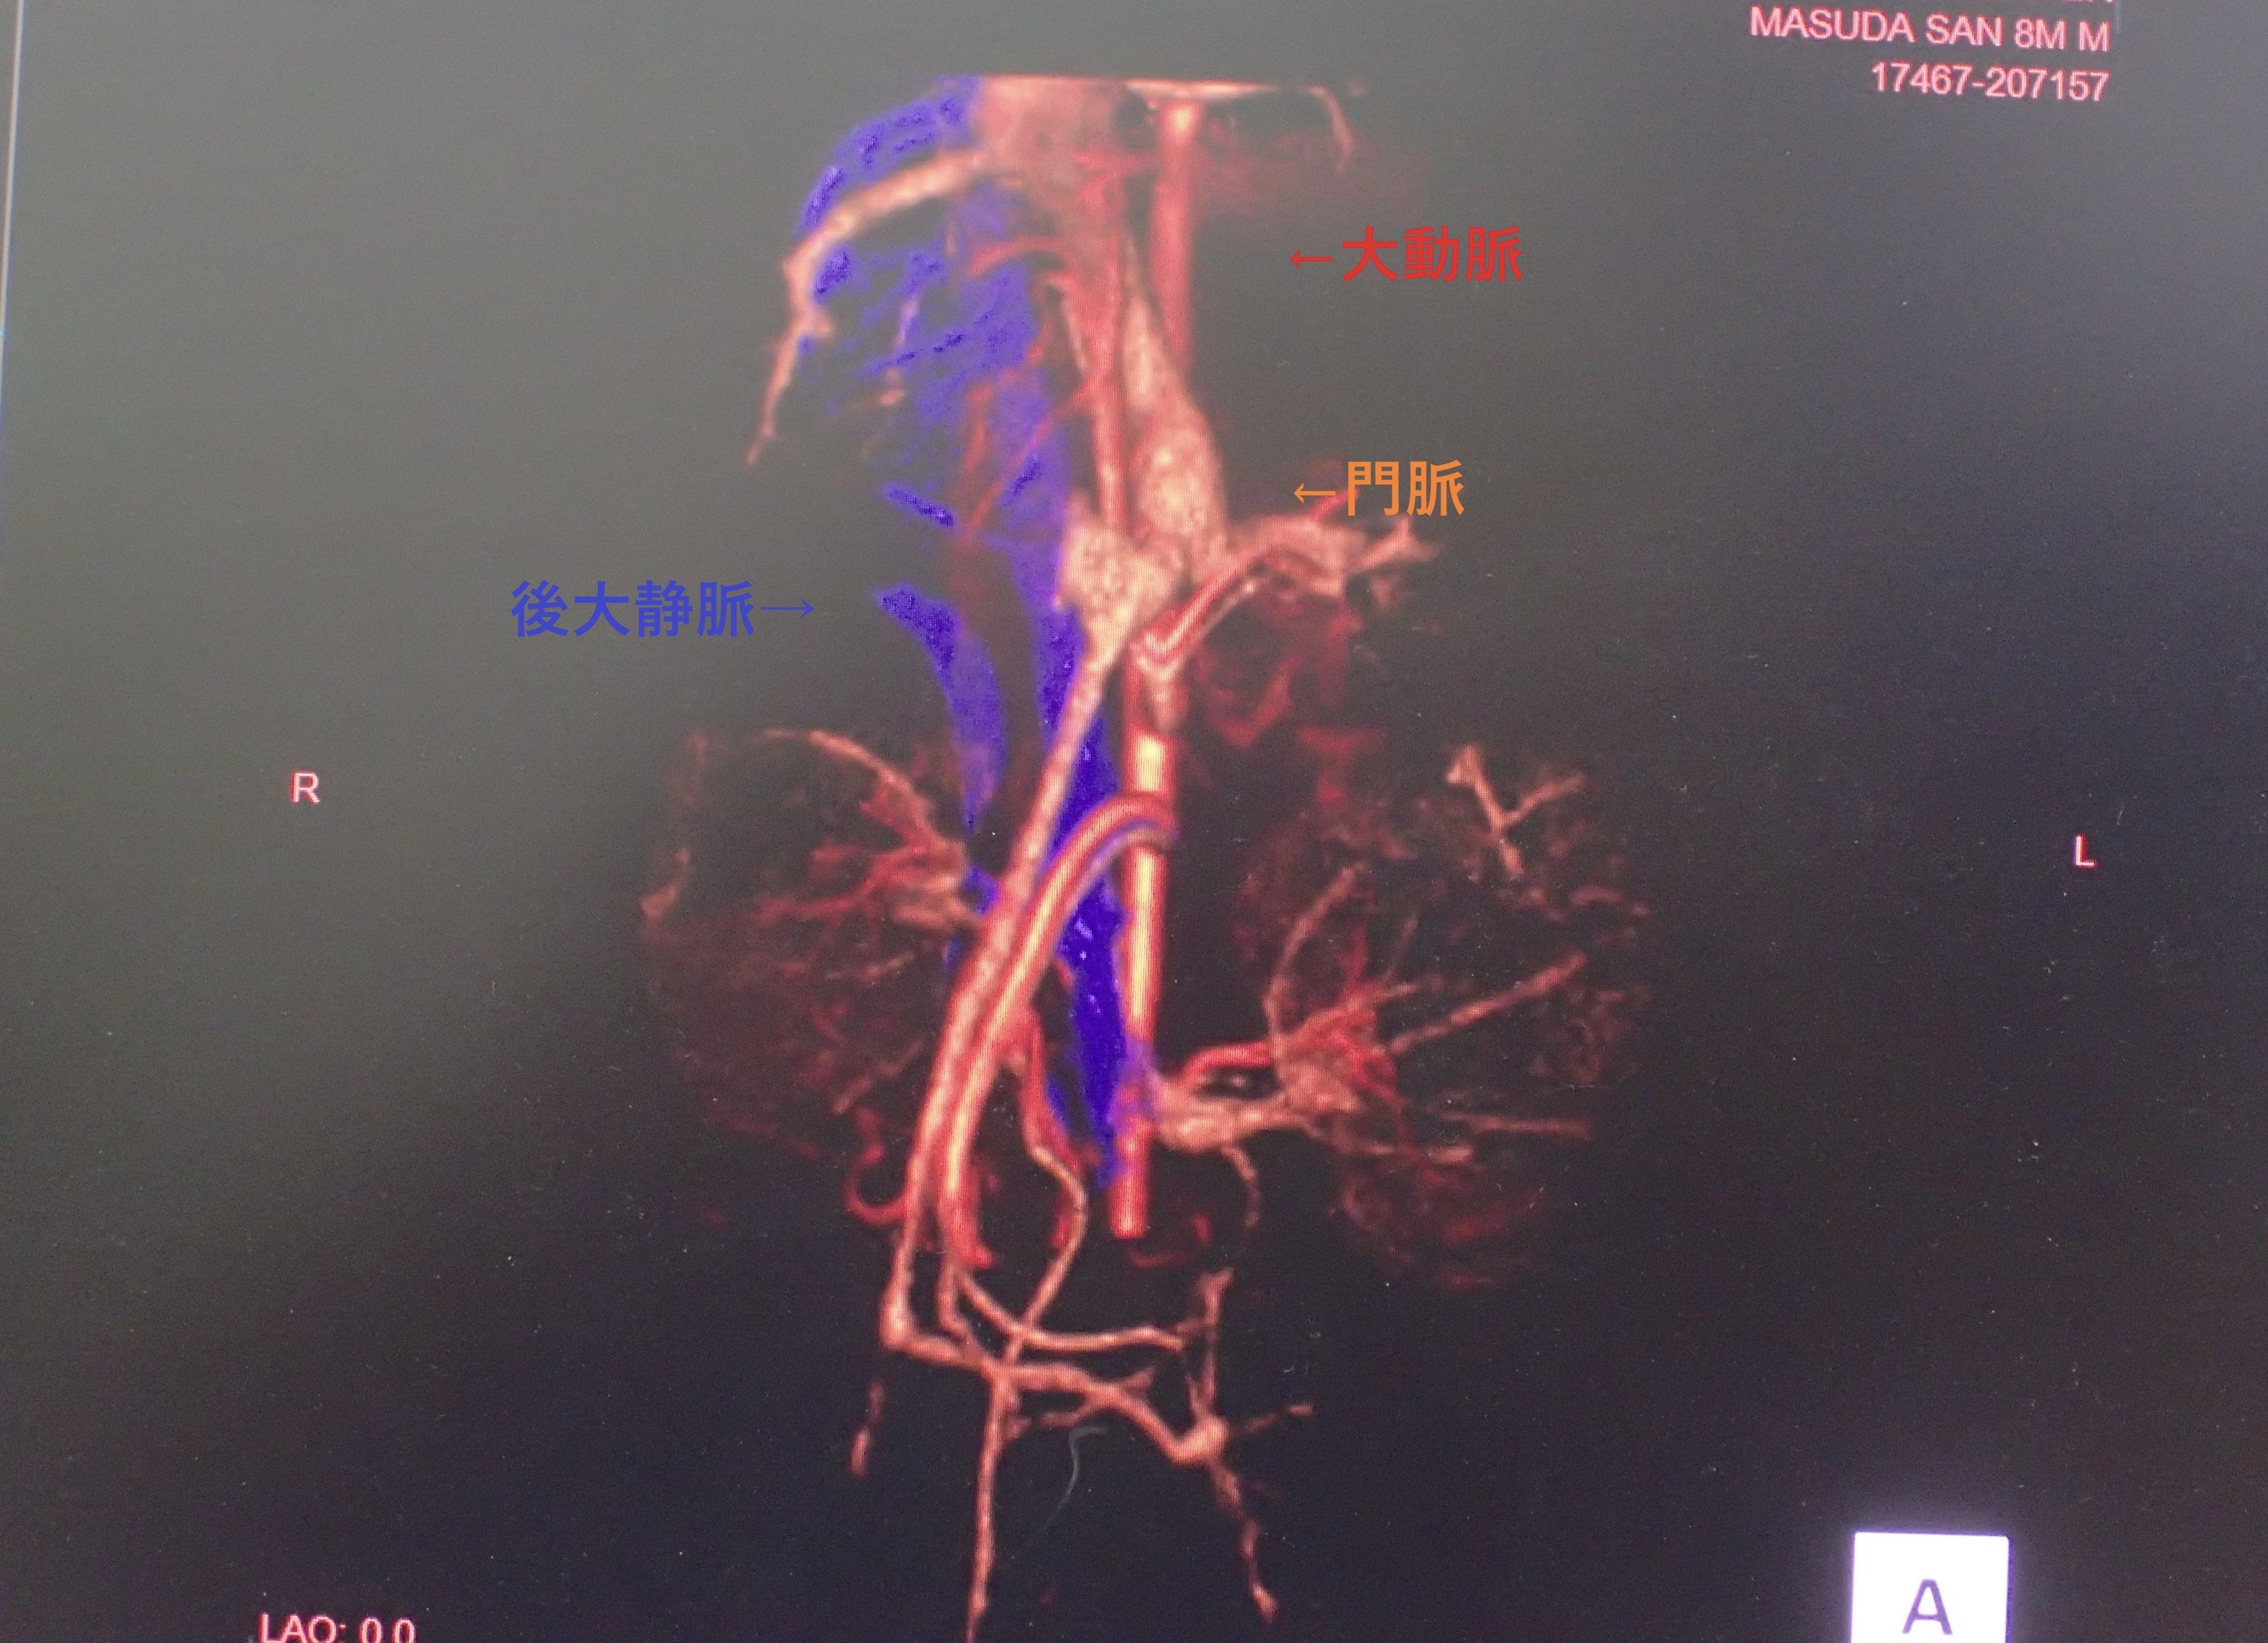

1月28日、専門の機器が揃ってる病院で検査をしてもらう事に。

検査の結果、やはり「門脈シャント」と診断されました。

画像からは、門脈が後大静脈にシャントしている、という診断になるそうです。